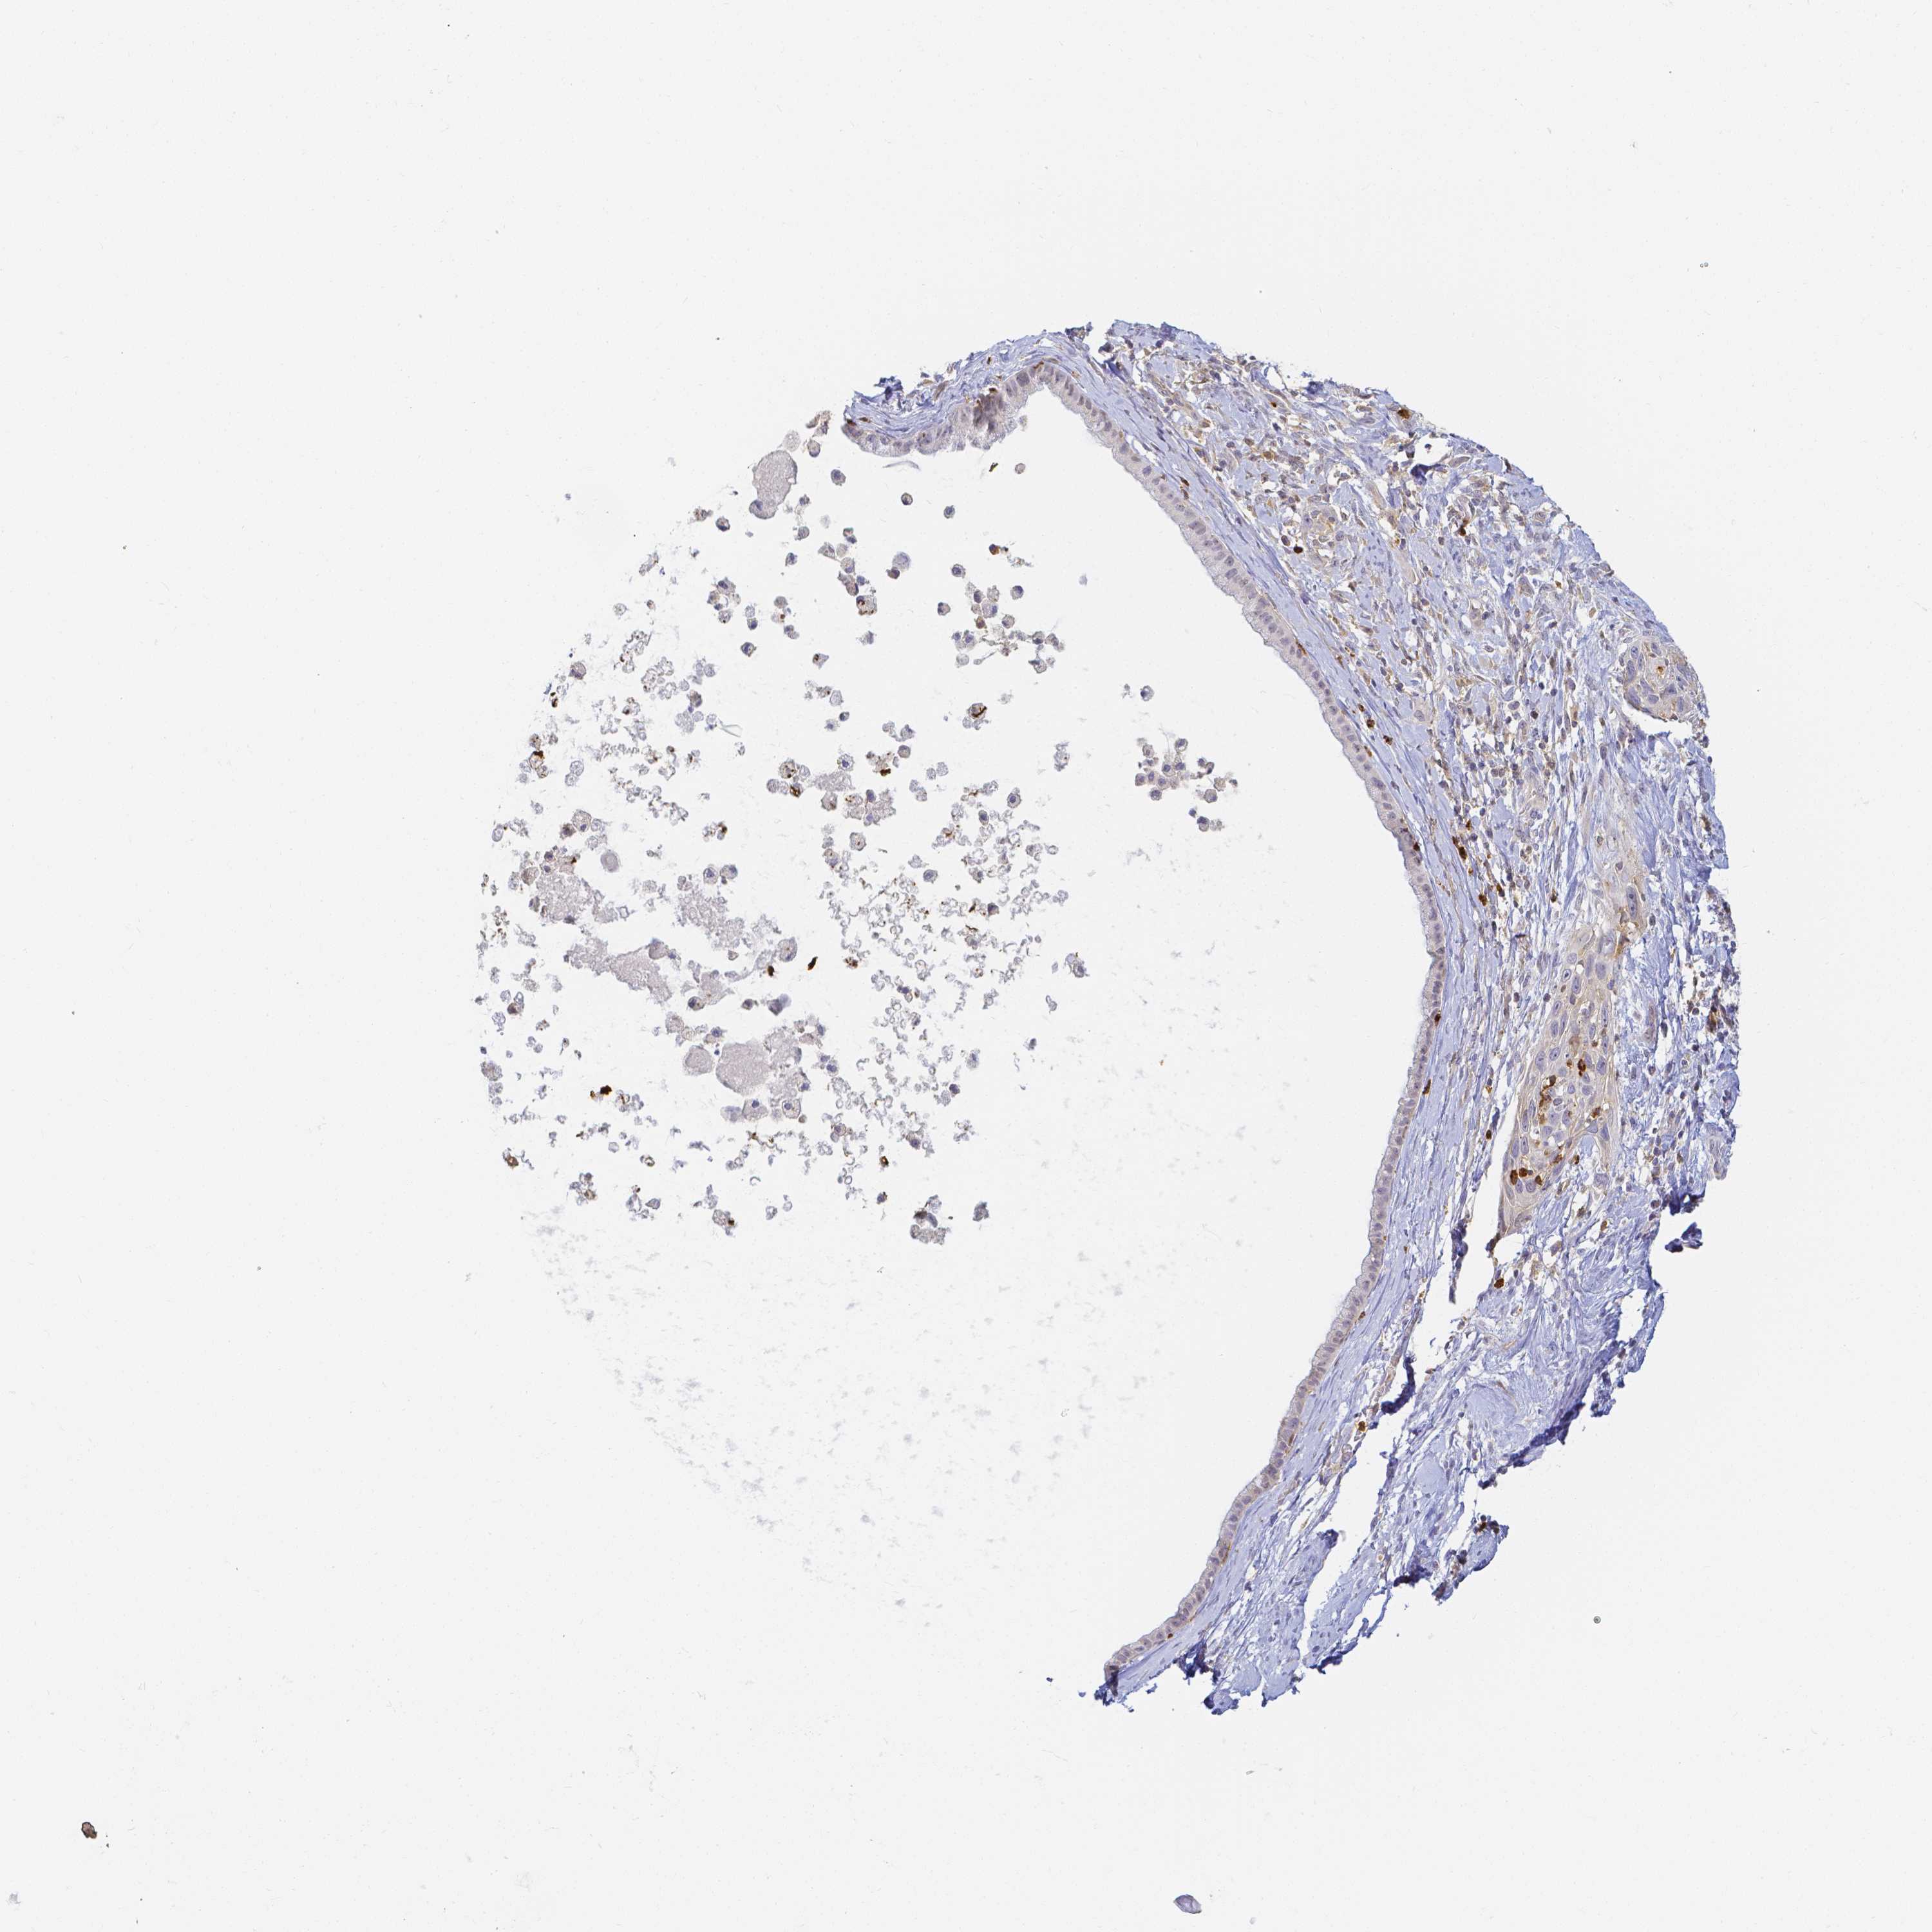

CERVICAL CANCER - Protein expressioni

A mouse-over function shows sample information and annotation data. Click on an image to view it in a full screen mode. Samples can be filtered based on level of antibody staining by selecting one or several of the following categories: high, medium, low and not detected. The assay and annotation is described here.

Note that samples used for immunohistochemistry by the Human Protein Atlas do not correspond to samples in the TCGA dataset.

Antibody stainingi

Antibody staining in the annotated cell types in the current human tissue is reported as not detected, low, medium, or high, based on conventional immunohistochemistry profiling in selected tissues. This score is based on the combination of the staining intensity and fraction of stained cells.

Each image is clickable and will lead to virtual microscopy that enables deeper exploration of all samples and also displays staining intensity scores, fraction scores and subcellular localization as well as patient and tissue information for each sample.

Antibody HPA019445

Antibody HPA076421

Staining

High

Medium

Low

Not detected

Intensity

Strong

Moderate

Weak

Negative

Quantity

>75%

75%-25%

<25%

None

Location

Nuclear

Cytoplasmic/membranous

Cytoplasmic/membranous,nuclear

Squamous cell carcinoma, NOS

Adenocarcinoma, NOS